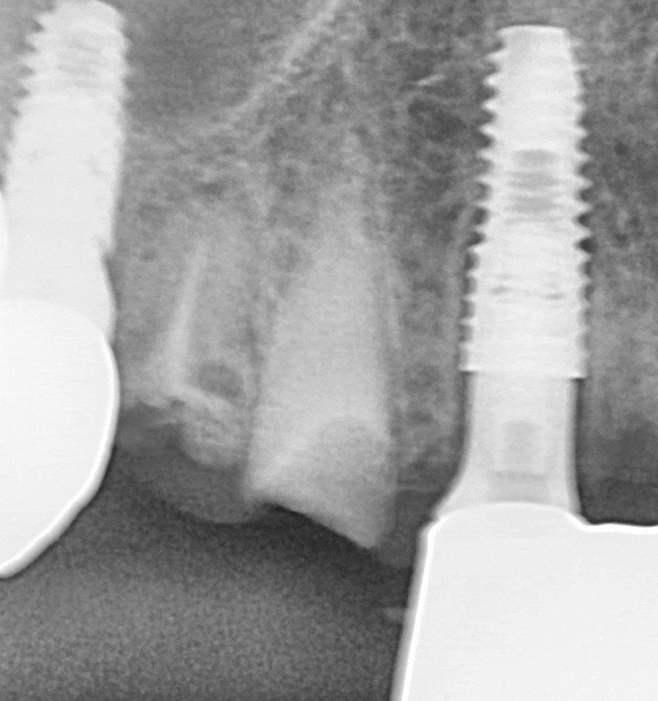

다행히 CT에서 확인했을 때

뼈의 높이와 두께가 비교적 괜찮아

뼈이식 없이 임플란트를

식립할 수 있었습니다.